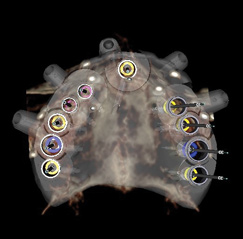

Fig 9. CT guided surgery planning. Ten implants were planned, including a maxillary anterior implant to be placed in the anterior nasal spine.

Figure 9